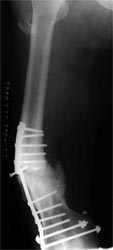

骨髓细胞与骨折愈合:骨髓中骨祖细胞可转化为成骨细胞,具有促进骨修复的作用,应用于临床也取得满意的效果。用髓内钉固定后保证早期稳定性,植骨补充成骨所需基质,骨髓骨祖细胞,可分化成为骨痂组织,骨生长因子促进骨折处再血管化,促进了骨不连的愈合。 病例介绍 病例一、患者63岁,股骨髁上骨折骨不连10年,曾先后4次手术,均采用钢板固定均松脱或折断而失败。 我们采用逆行髓内钉内固定,以及骨髓细胞复合生长因子植骨术,术后1年X线片连续性骨痂形成,膝关节功能良好。